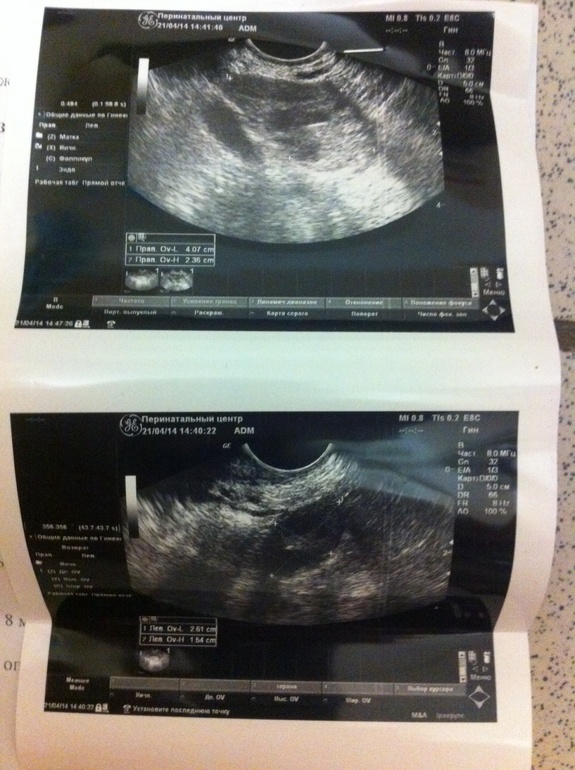

Девочки миленькие... Сегодня 16 ДЦ по ощущениям О была на 14-15 ДЦ, ПА был только в ночь с 15 на 16 ДЦ ... Посмотрите пожалуйста мое узи... Была овуля? Девочки я не верю в счастье свое.... Какие шансы, как думаете? Очень переживаю... Может дюф начать пить?

Если желтое тело есть, значит была! Да и свободная жидкость об этом говорит. А дюфастон без назначения не стоит, можно себе цикл сбить, лучше сдать прогестерон на 7 дпо, тогда видно будет, надо ли чего добавлять. Удачи!

Вроде да, была в правом! Спрошу шепотом: "А почему вверх тормашками? Шифруетесь?"

Если через 3 дня переделаешь узи, то эндометрий будет около 12-13 мм, и ЖТ не менее 16-17 мм. Жидкость исчезнет или останется 4-5 мл.

дюф начинай, жидкость 15 мм, это отлично, что говорит что возможно вот прямо за несколько часов до узи произошла, ЖТ через 3 дня подрастет, оно только образовываться начало! 100 % овуляция

овуляция произошла вот вот недавно